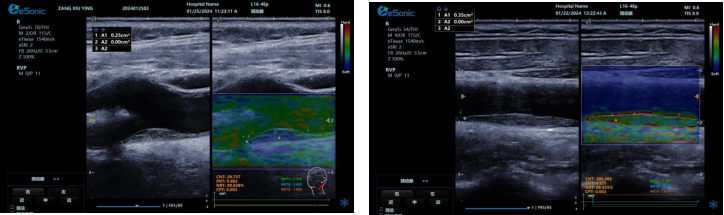

image.png

? 定量评估上,提供 CNTENTNRTCPT 等指标和参数,为监测老年颈动脉斑块风险提供客观准确依据。

? 借助 AI 自动分析,可快速筛选诊断,提升脑卒中筛查效率,有望重塑易损斑块临床诊断流程。

相比传统超声弹性成像技术,RVP 利用颈动脉搏动采集数据,避免了操作者施压等主观因素干扰,数据处理更精准,结果重复性佳,不受操作者差异影响。